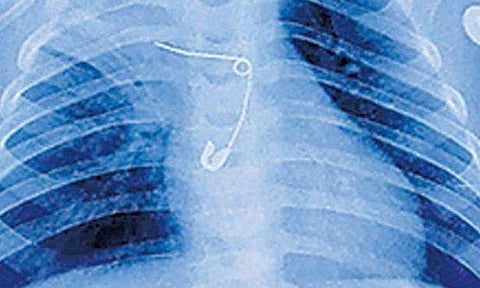

സുചി വിഴുങ്ങിയ കുഞ്ഞിന്റെ എക്‌സറേ ചിത്രം

മുളങ്കുന്നത്തുകാവ്: സൂചി വിഴുങ്ങിയതിനെ തുടർന്ന് ആരോ​ഗ്യനില മോശമായ കുഞ്ഞ് ജീവിതത്തിലേക്ക്. സുചി വിഴുങ്ങിയതിനെ തുടർന്ന് എട്ട് മാസം പ്രായമായ കുഞ്ഞ് അന്നനാളം, ശ്വാസകോശം, തലച്ചോറ് എന്നിവയ്ക്ക് അസുഖം ബാധിച്ചാണ് മെഡിക്കൽ കോളജ് ആശുപത്രിയിൽ ചികിത്സ തേടിയത്.

സേഫ്റ്റി പിൻ പുറത്തെടുക്കാൻ ഡോക്ടർമാർക്കായി.  ജനുവരി 19നാണ് മണ്ണുത്തി വല്ലച്ചിറ വീട്ടിൽ വിനോദ് - ദീപ ദമ്പതികളുടെ മകനെ അബോധാവസ്ഥയിൽ മെഡിക്കൽ കോളജ് ആശുപത്രിയിൽ എത്തിച്ചത്. പ്രതിരോധ കുത്തിവയ്പിന് കൊണ്ടുപോയപ്പോൾ കുഞ്ഞ് രക്തം ഛർദ്ദി. ആശുപത്രിയിലേക്കുള്ള യാത്രയ്ക്കിടെ ഒരു വശം തളരുകയും അബോധാവസ്ഥയിലാവുകയും ചെയ്തു.

ഇതിന് ശേഷം നടത്തിയ പരിശോധനയിലാണ് അന്നനാളത്തിൽ സൂചി കണ്ടെത്തിയത്. മൂന്നാഴ്ചത്തെ പരിചരണത്തിനു ശേഷം ഇപ്പോൾ വെന്റിലേറ്ററിന്റെ സഹായമില്ലാതെ ശ്വസിക്കുന്നതിനും ഭക്ഷണം ഇറക്കുന്നതിനും കുഞ്ഞിന് കഴിയുന്നുണ്ട്.